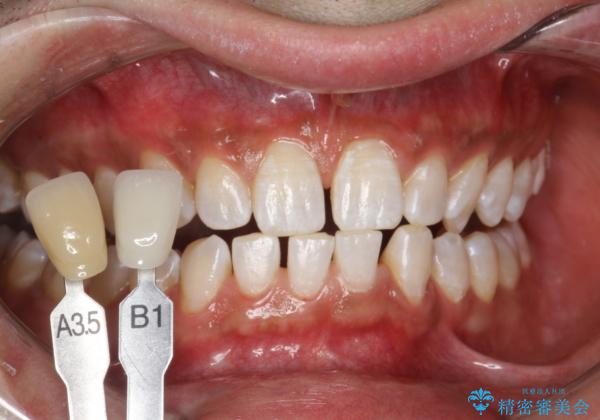

- ホワイトニングで、できる限り白くしたいとのことで来院されました。処置前クリーニング(¥3,300)・エクセレントホワイトニング(¥29,700)・トリートメント(¥550)を行いました。